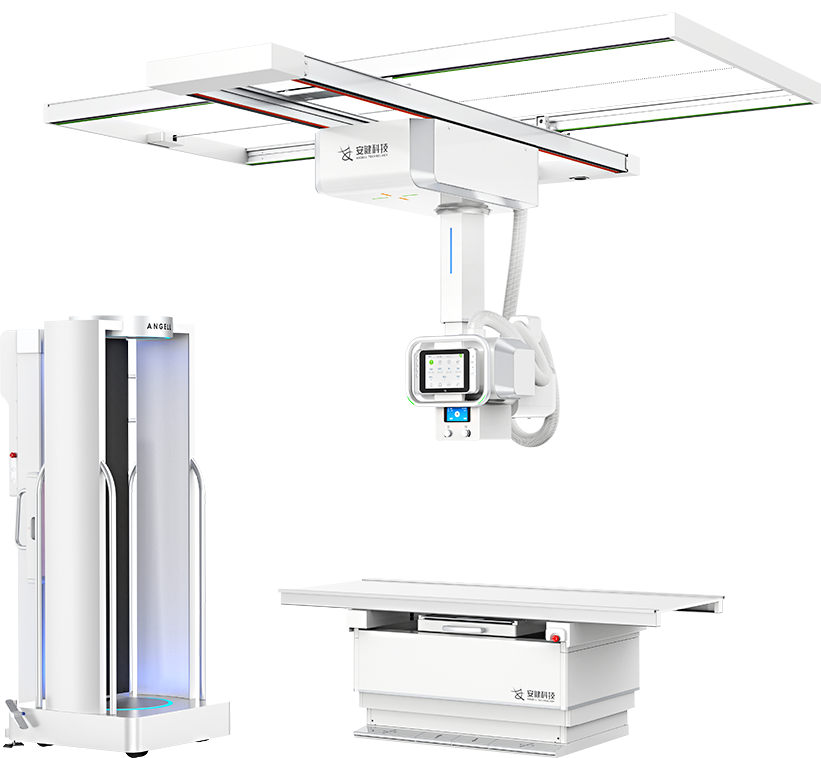

國內(nèi)首創(chuàng)真三維數(shù)字化X線攝影系統(tǒng)

全身覆蓋

最大350mm FOV

可移動式站臺設(shè)計